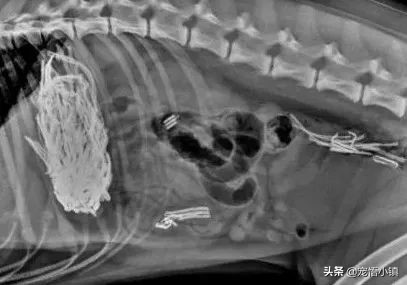

如果玩具较小,一直没有找到的话,那么很有可能在狗狗的肚子中!怀疑的话,带着狗狗拍片,随后就会发现:

(勺子?!!!)

(玩具车?!!!)

(绳结玩具?!!!)